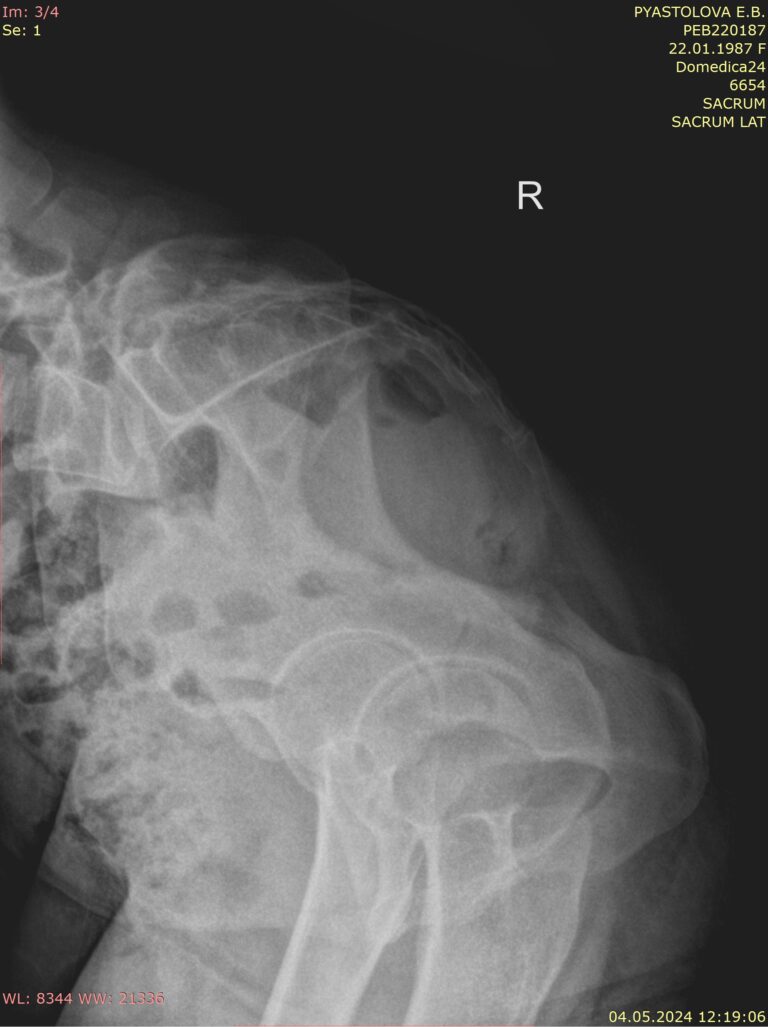

На снимках сравнивается положение копчика сидя и стоя. Для этого врач определяет (чертит) на снимках крестцово-копчиковый угол, который в норме составляет около 150о. Также проводится дугообразная линия через центр копчиковых позвонков:

• Здоровый копчик отклоняется кпереди или кзади на 5-20о или примерно 2 см при сидении и возвращается обратно при стоянии;

• При гипермобильности, посттравматической или идиопатической, то есть ни с чем не связанной, отклонение будет чрезмерным ― больше 25о. А сам угол при этом уменьшается от 140 до 90о;

• При подвывихе происходит смещение сегмента копчика кзади или кпереди, на дугообразной линии видна ступенька;

• При сращении с крестцом копчик будет неподвижен ― неизменен на обеих рентгенограммах;

• Также на снимке могут быть видны: переломы, новообразования, костные разрастания, отек мягких тканей.

Выполняется 2 теста:

• В положении сидя боком к экрану;

• В положении стоя, так же боком, то есть в обычной боковой проекции. Иногда этот снимок выполняется, когда пациент лежит.